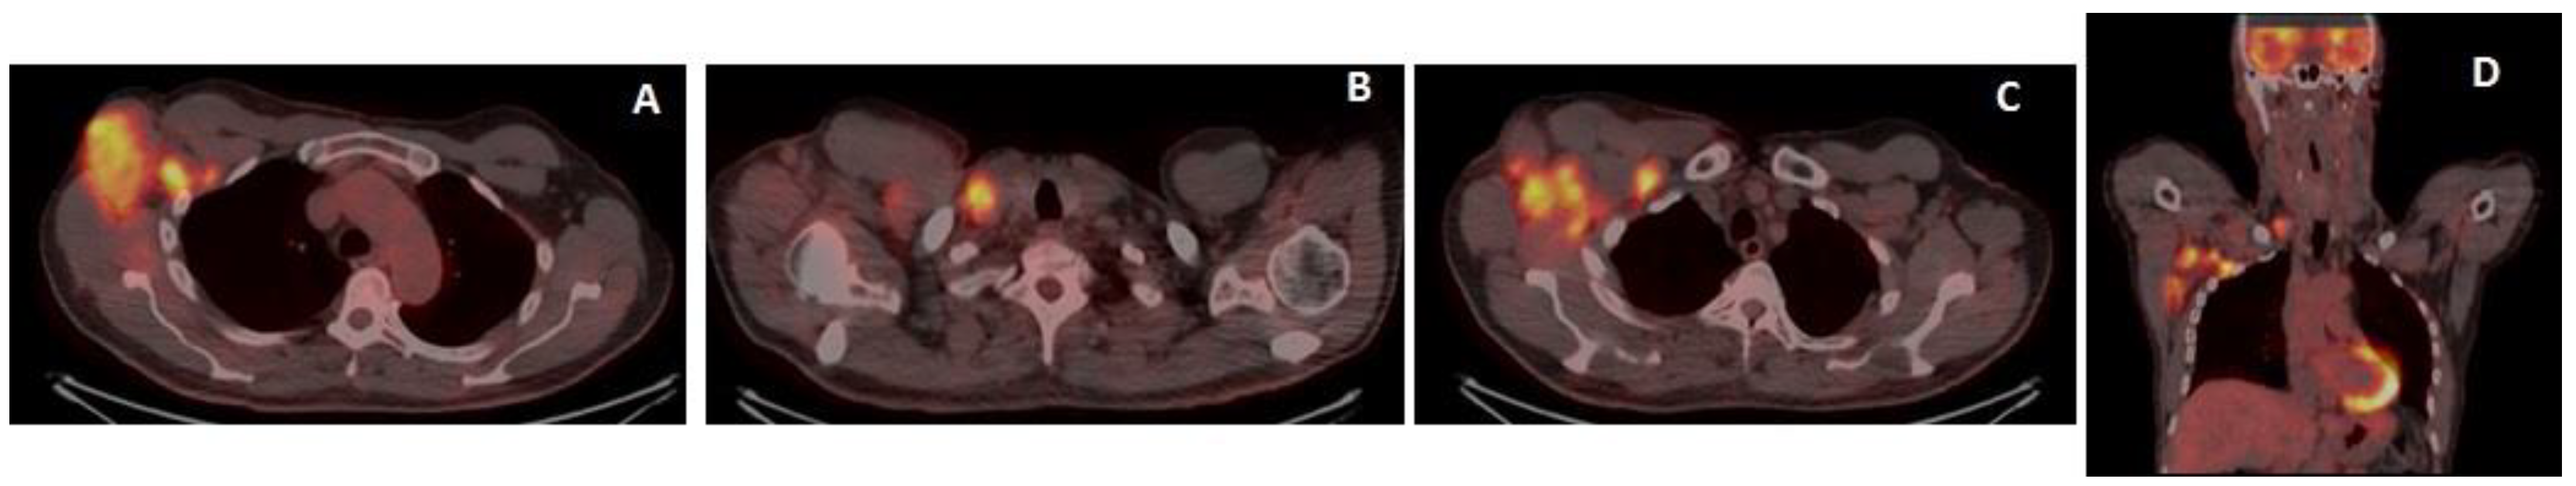

2. Case Report